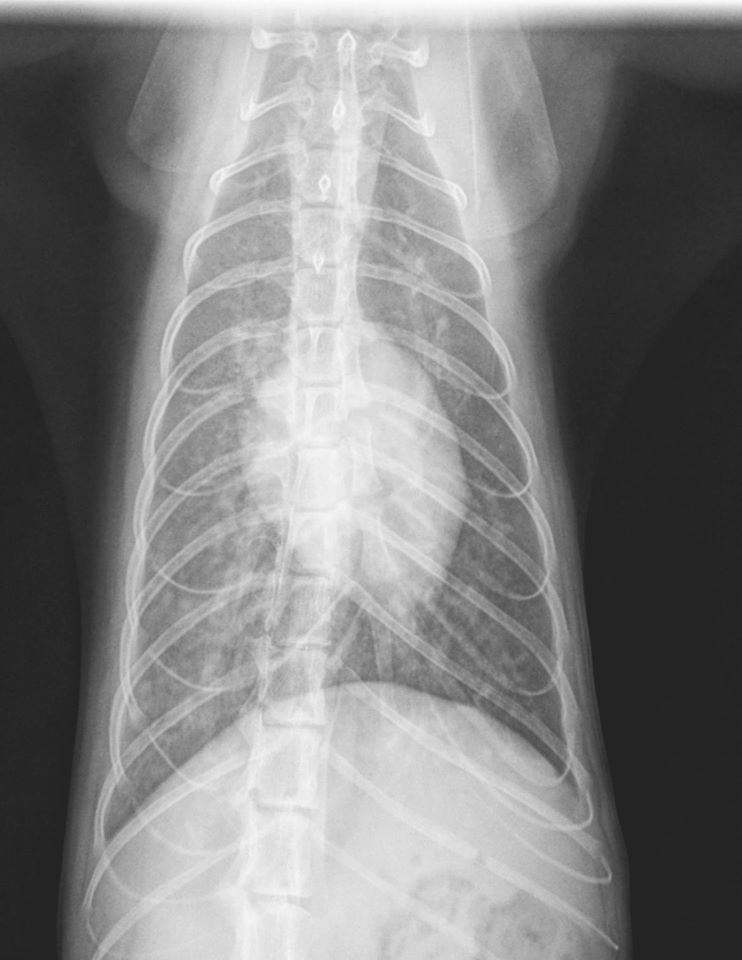

- Image interpretation is what we do all day long, and we are good at it!

- There is a high incidence of over-interpretation of common imaging findings (perceived loss of abdominal detail, splenomegaly, interstitial pattern, etc.). We can help tell you whether these findings are significant and need further evaluation.

- Significant findings are often overlooked because they are not recognized in the images. This is one of the primary reasons to use us!

- It is always a good idea to have at least two people (you and us) evaluate images in a team-based approach.

- Having all of your studies interpreted is taking the quality of medicine you practice to the next level.